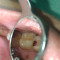

Karies gigi pada pasien dengan riwayat DM tipe 1 disertai mata yang berdenyut

Alodokter, Pasien Tn X usia 23 th, karies pada gigi kanan atas regio 16,17 terjadi pembengkakan hingga meluas ke spasia bukal meluas ke infra orbital. Pasien...

Penanganan yang tepat untuk mengatasi bleeding pada karies proximal

Alo dokter 😊 Saya ingin mendiskusikan kasus saya.. Pasien dtg dengan keluhan gigi sering terselip makanan.Pemeriksaan klinis gigi 25, karies proksimal...